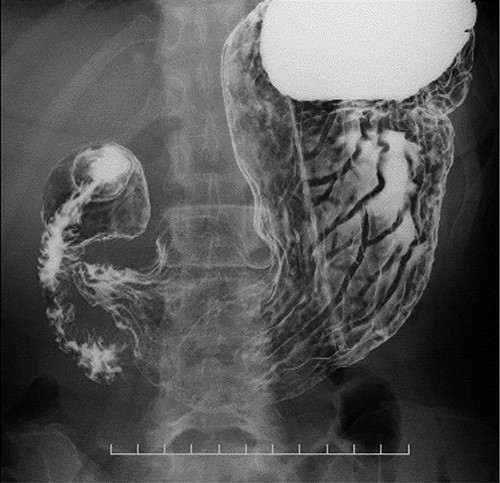

Preoperative computed tomography (CT) and barium meal studies were performed. The CT findings showed circumferential wall thickening with infiltrative change at the middle of the intrathoracic esophagus, with luminal dilation of the oral side of the stenotic esophagus (Figs 2, 3). The barium meal study showed no abnormal findings in the stomach (Fig. 4). Thoracoscopic esophagectomy was performed with the patient in the semi-prone position, followed by esophageal reconstruction using a gastric tube with the patient in the supine position. The operation was started with bilateral lung ventilation using a single-lumen endotracheal tube. A four-port thoracoscopic technique was used as follows: an observation port with a 10-mm scope was placed at the ninth intercostal space at the line of the inferior scapular angle, and two 5-mm ports and one 12-mm port for the intrathoracic procedures were placed at the third, fifth and seventh intercostal spaces, respectively, at the posterior axillary line (Fig. 5). Pneumothorax was created using 10 mmHg of CO2 to deflate the lung to achieve a better operative field. The pleura and connective tissue around the thoracic esophagus showed severe inflammatory and fibrotic changes. In particular, the middle thoracic esophagus was strongly adherent to the arch of the azygos vein and the tracheal bifurcation.

Coronal plane of the CT findings; CT demonstrates dilatation of the upper thoracic esophagus.